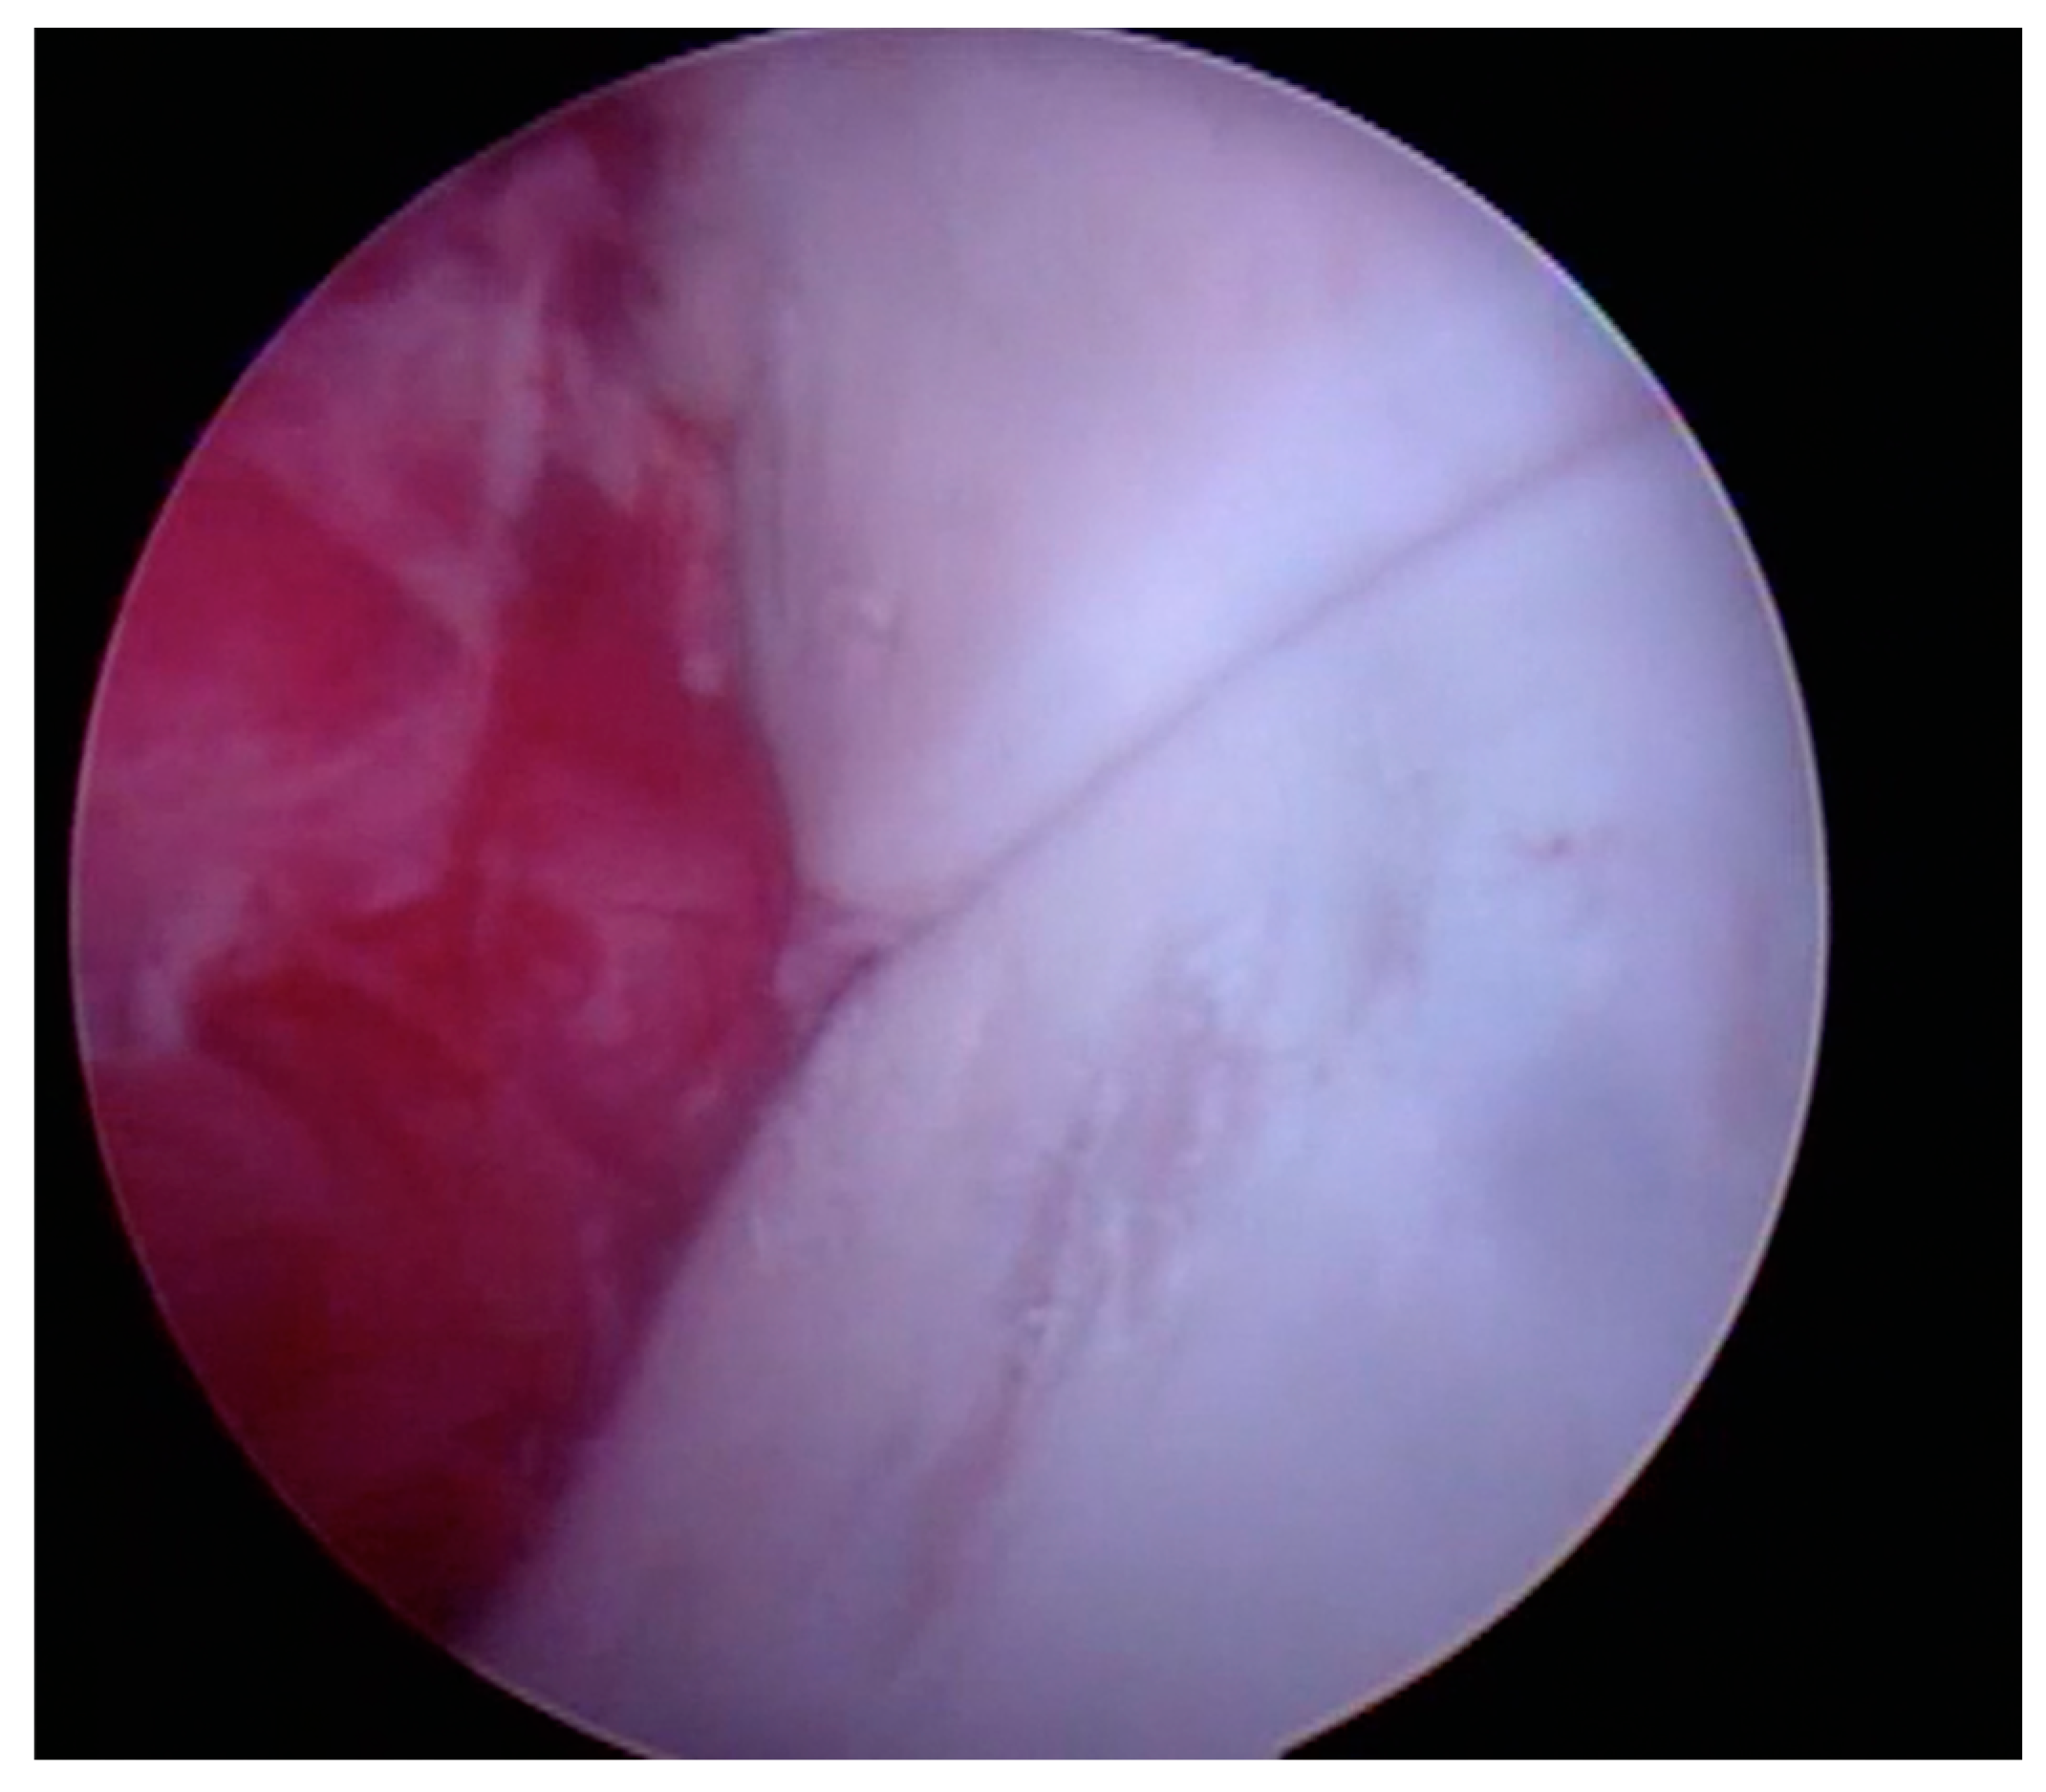

- Loss of gloss of the articular surface (Figure 1)

- Softening of the articular surface (Figure 2)